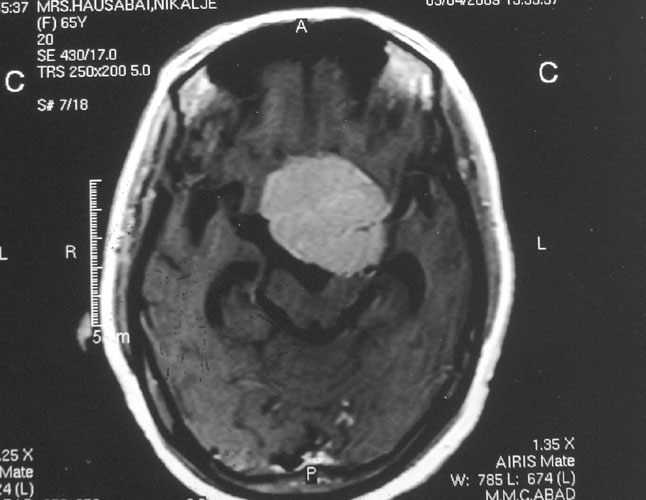

Intracranial Meningiomas

Meningiomas are solid, nodular (rarely, cystic), benign tumors that arise from the coverings of the brain, and compress the adjacent brain tissue. Usually present with headache, visual disturbances or weakness of half of the body. Diagnosis is by progression, especially if the tumor removal has been incomplete. Diagnosis is by MRI and surgery is curative.